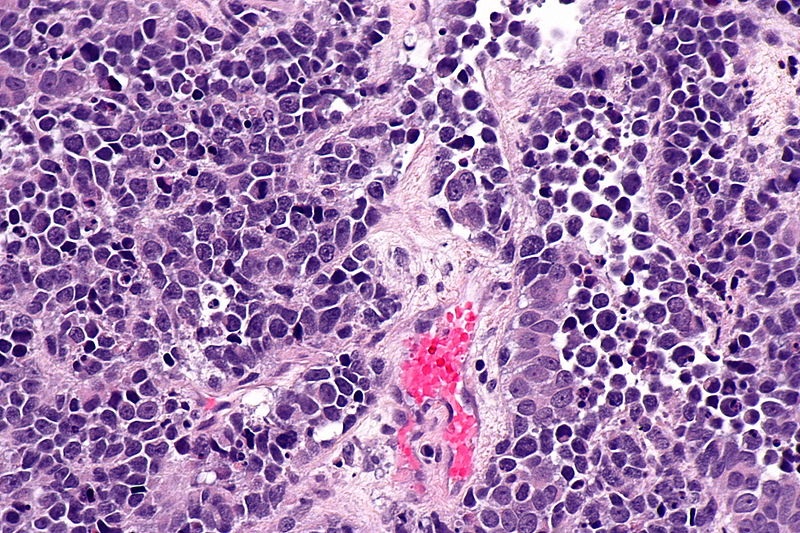

A study conducted by researchers from the University of Surrey in England was recently published in the Clinical Cancer Research medical journal. The research focuses on patients with non-muscle invasive bladder cancer.

The researchers use CAVATAK, virus-based immunotherapy that is practically composed of live common cold virus called the coxsackievirus A21. It is known for its ability to kill or cause damage to various types of cancer cells, so using it in developing cancer immunotherapies is not new. However, this particular study has seen some success as of its publication.

Researchers observed that the virus, whether administered alone or combined with mitomycin C, was able to reproduce and specifically attacked cancer cells without causing harm to other cells in a patient’s system. The scientists reportedly saw the majority of the patients’ tumor eventually killed while one of them saw “complete resolution.” The study also reads, “No significant toxicities were reported in any patient, from either virus or combination therapy.”